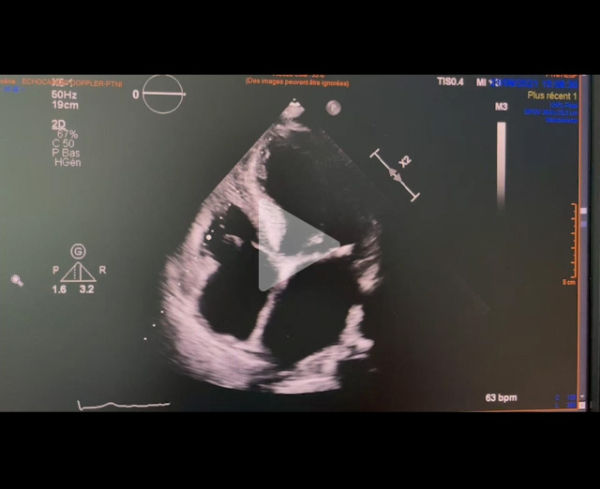

Echographie cardiaque transthoracique : PSGGA

Vidéo 2

Paramètres échographiques